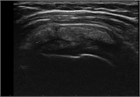

1. 急性の石灰沈着性滑液包炎は、腱板内に沈着した石灰が肩峰下滑液包へ流出して発生する結晶性滑液包炎である。突然発症する例が多い。

1. 腱板内に沈着した石灰が大きくなり、慢性化してインピンジメント症状や関節拘縮を引き起こすこともある。

1. 無症候性の石灰沈着症の発生率は人口の2.7~20%で、30~50歳に好発する。有症状の沈着症は50歳前後であり、女性(男女比は3:2)と棘上筋腱に多い。